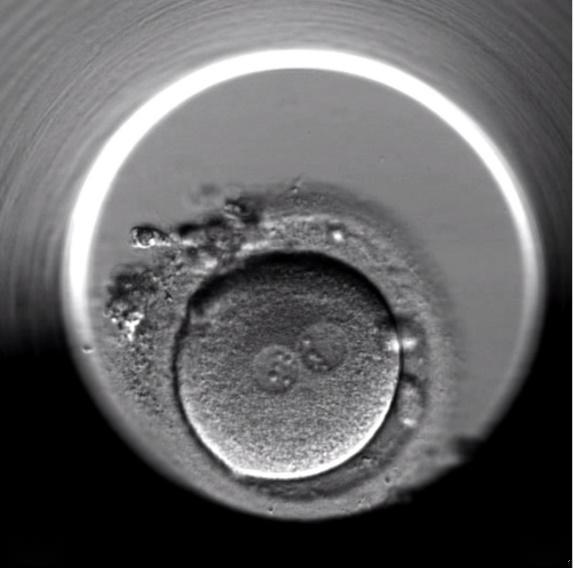

第三步:受精官宣16-18小时后看到2个原核(1个来自卵子、1个来自精子),大小对称=正常受精

囊胚结构图解